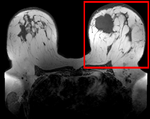

Registration Library Case #6: Breast MRI Treatment Assessment

| fixed image/target pre Rx MRI |

moving image post Rx MRI |

We seek to align the post-treatment (PostRx) scan with the pre-treatment scan to compare local effects (left side only).

unregistered

after affine registration

after nonrigid (BSpline) registration

- soft tissue deformations during image acquisition cause large differences in appearance

- the large tumor recession represents a significant pre/post difference in image content that will influence unmasked intensity-driven registration, which becomes a problem for the non-rigid portion of registration, particularly at higher DOF, because the registration will try to "recreate" the tumor area from the postRx image in order to match the content.

- contrast enhancement and pathology and treatment changes cause additional differences in image content